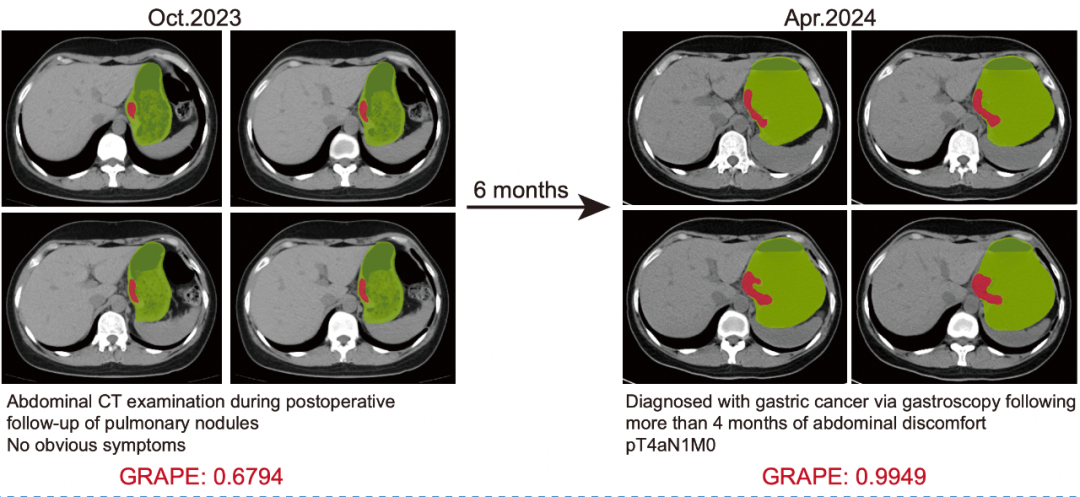

最让人惊喜的是它能提前发现。研究里有个案例,2024年4月一名患者被确诊为局部晚期胃癌。医生回头把他6个月前做过的CT影像拿给AI分析,结果AI当时就提示有早期胃癌病灶。如果当时就发现,这患者就能提前半年治疗,结局可能完全不同。